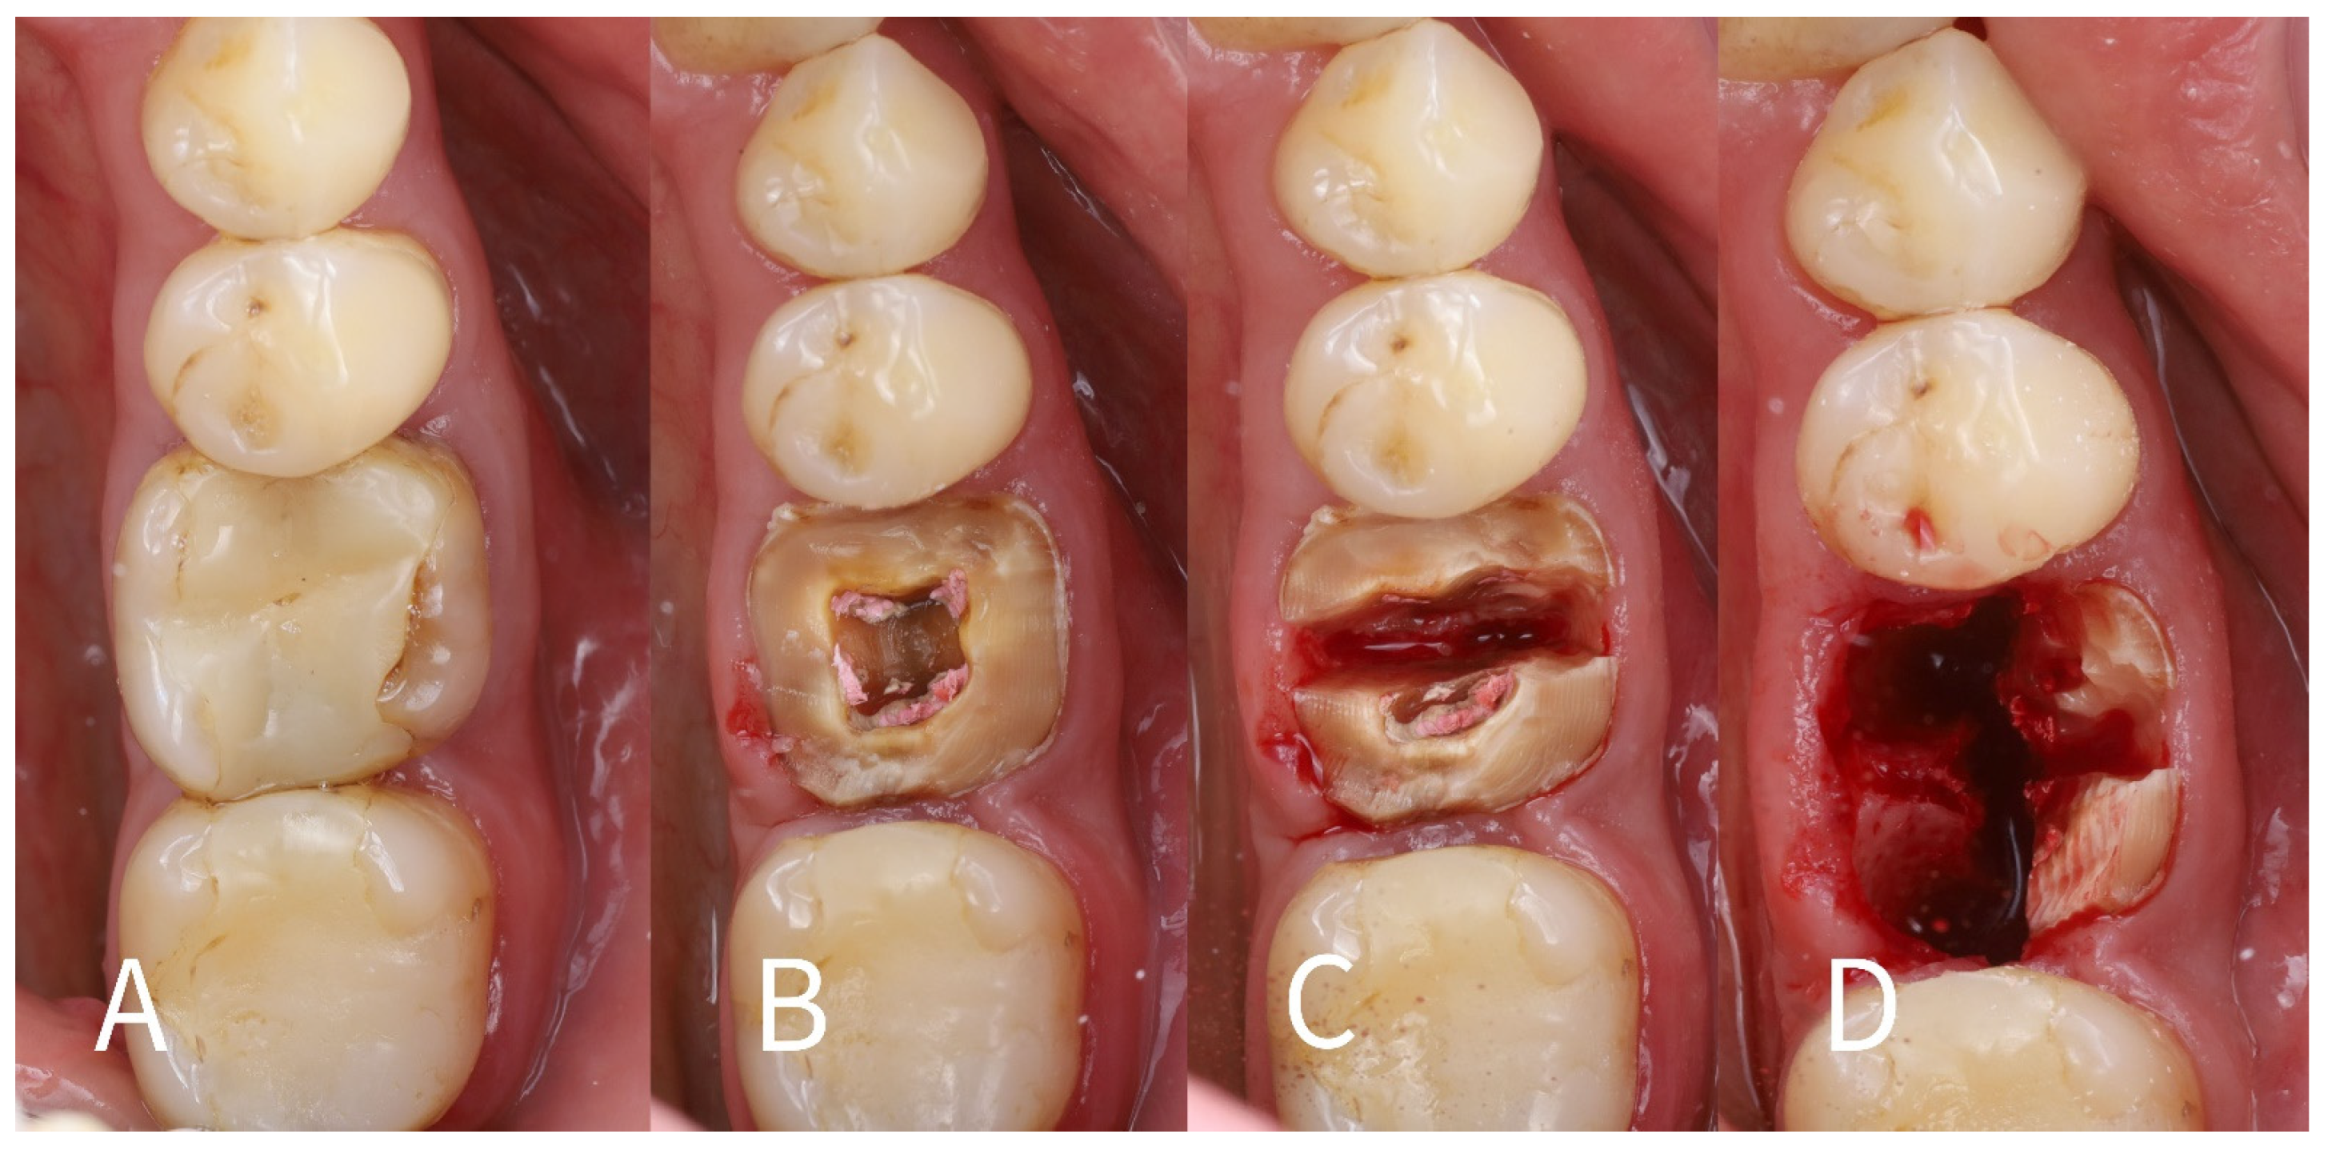

- Root sectioning: After performing mandibular nerve block anesthesia, the crown of tooth #36 (Figure 2A) was removed (decoronation was performed) (Figure 2B). The mesial and distal roots were then separated buccolingually using a long-shanked, straight diamond bur in a high-speed handpiece with copious irrigation (Figure 2C). The preoperative CBCT was consulted to guide the depth and orientation of the cuts, accounting for the roots’ length, curvature, and angulation.

- Partial root extraction: Each root was sectioned in a mesiodistal direction approximately 1–1.5 mm buccally from the center of each root surface to a depth of about two-thirds of the root length, using a #2 long cylinder bur from Gluckman’s partial extraction therapy (PET) surgical kit (Megagen, Seoul, South Korea). This created buccal and lingual segments for each root. The lingual root segments (along with their apices) were carefully extracted, leaving only the buccal portions of the roots in place as the “socket shields” (Figure 2D). If the lingual part fails to extract and remains in the socket still attached to the shield, it should be detached from the shield with bur #3 and extracted in the conventional way. In such cases, the bony septum can be drilled in the center to facilitate extraction.